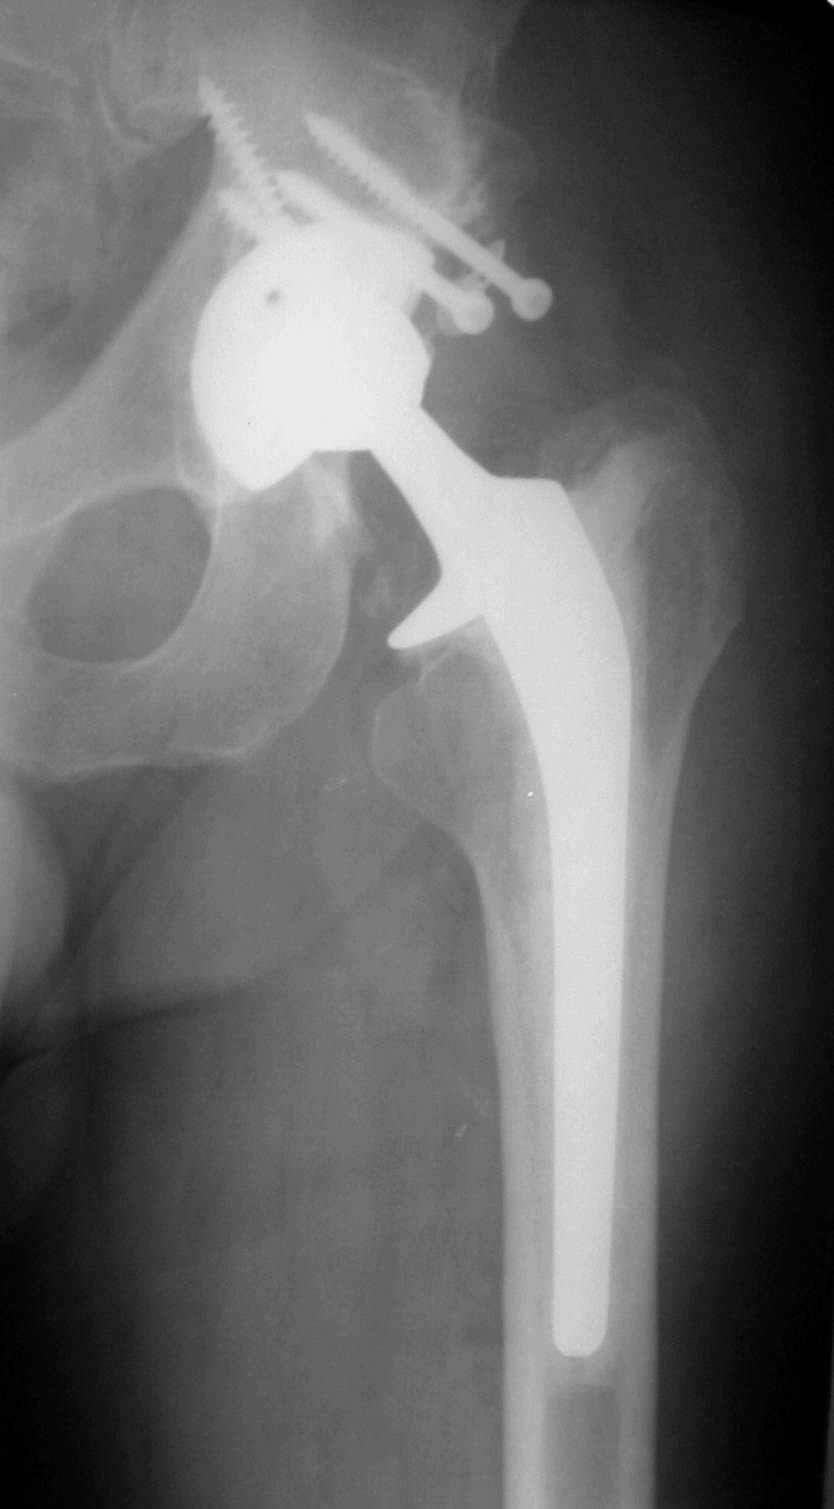

В институте совместно с фирмой Зиммер достаточно регулярно (практически ежемесячно) проводятся 2-х недельные циклы по различным вопросам эндопротезирования. Если есть возможность и желание, мы готовы поделиться с Вами нашим опытом, тем более есть что показать и что обсудить - в настоящее время ежедневно выполняется от 6 до 10 эндопротезирований коленного и тазобедренного сустава. В качестве примеров хочу показать 2 наблюдения, через 1 год и 5 лет после операции

С уважением, Р.Тихилов

1 год

5 лет